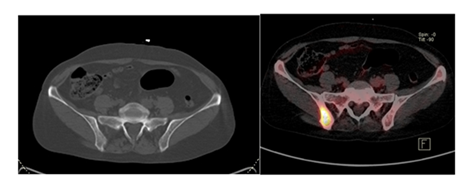

Our patient was a 65-year-old female diagnosed with Grade III ER-/PR-/Her-2 invasive ductal carcinoma in the left breast. She underwent neoadjuvant chemotherapy, followed by left mastectomy and radiotherapy. Six months after completion of therapy, the patient presented for a routine clinical evaluation and underwent a follow-up 18F-FDG PET/CT examination. At the time of referral, the patient reported mild persistent pain in the right upper limb, without a history of trauma. The laboratory tests showed normal platelet counts, hemoglobine and white blood cells, mild elevation of alkaline phosphatase. In addition, tumor marker CA 15-3 was above the normal refrence range 68U/mL, while CEA was normal. Liver and renal function test were within the normal limits. The 18F-FDG PET/CT images identified two focal areas of increased radiotracer uptake in the right iliac bone and the right femoral bone, both without noticable structural abnormalities on the CT. There were considered metabolically active but CT-negative bone lesions. Furthermore, a focal FDG-avid pulmonary lesion was detected, suspicious for lung metastases.